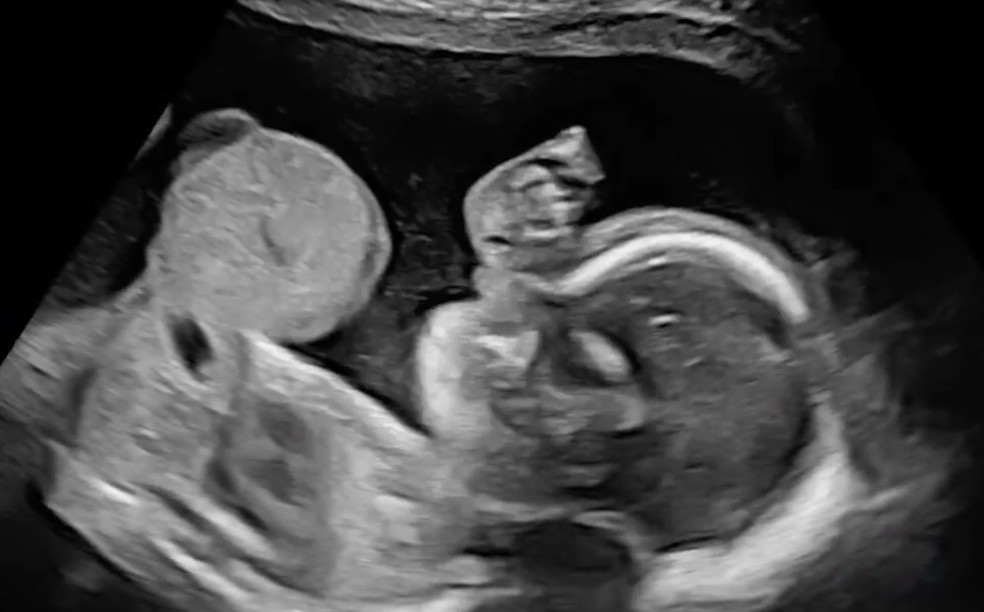

/i.s3.glbimg.com/v1/AUTH_1f551ea7087a47f39ead75f64041559a/internal_photos/bs/2026/e/8/ng0VkXTBeYJBV3PzNmbA/hendrix-no-utero.jpg)

Riley Alaya, mãe de Hendrix, descobriu a onfalocele do

filho durante o segundo trimestre da gravidez